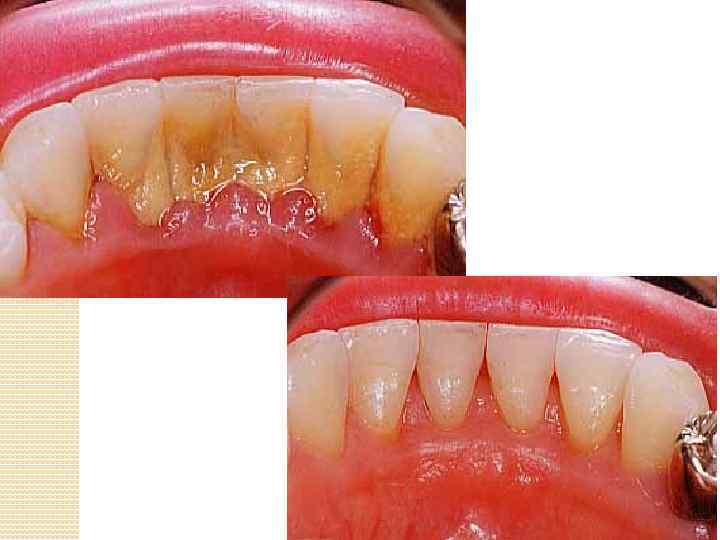

Зубной камень это минерализованный или находящийся на стадии минерализации зубной налет. Зубной камень состоит на 70 -90% из неорганических и на 10 -30% из органических компонентов. Зубной камень располагается над гребнем десневого края, и называется наддесневым. Он обычно белого, серого, желтого цвета, твердой консистенции. Наддесневой зубной камень минерализуется за счет попадания солей кальция из слюны на поверхность зубного налета.

Поддесневой зубной камень интенсивно растет внутрь по корню зуба, разрушая связочный аппарат периодонта (опорно-удерживающие связки зуба в челюстной кости). Впоследствии образуется зубодесневой карман - промежуток между десной и зубом, а в последующем - костный карман. От костного кармана и развиваются серьезные заболевания пародонта (опорноудерживающий аппарат зуба). Сначала развивается гингивит (воспаление десен), который постепенно переходит в пародонтит. Все это и впоследствии приводит к расшатыванию и потере совсем невинных зубов. Часто пародонтит именуют с "пародонтозом" устаревшее понятие для не воспалительного процесса атрофии кости челюсти. Напротив, при пародонтите речь идет, прежде всего, о воспалительном процессе.

Поддесневой зубной камень гингивит зубодесневой карман пародонтит костный карман расшатыванию и потеря зубов